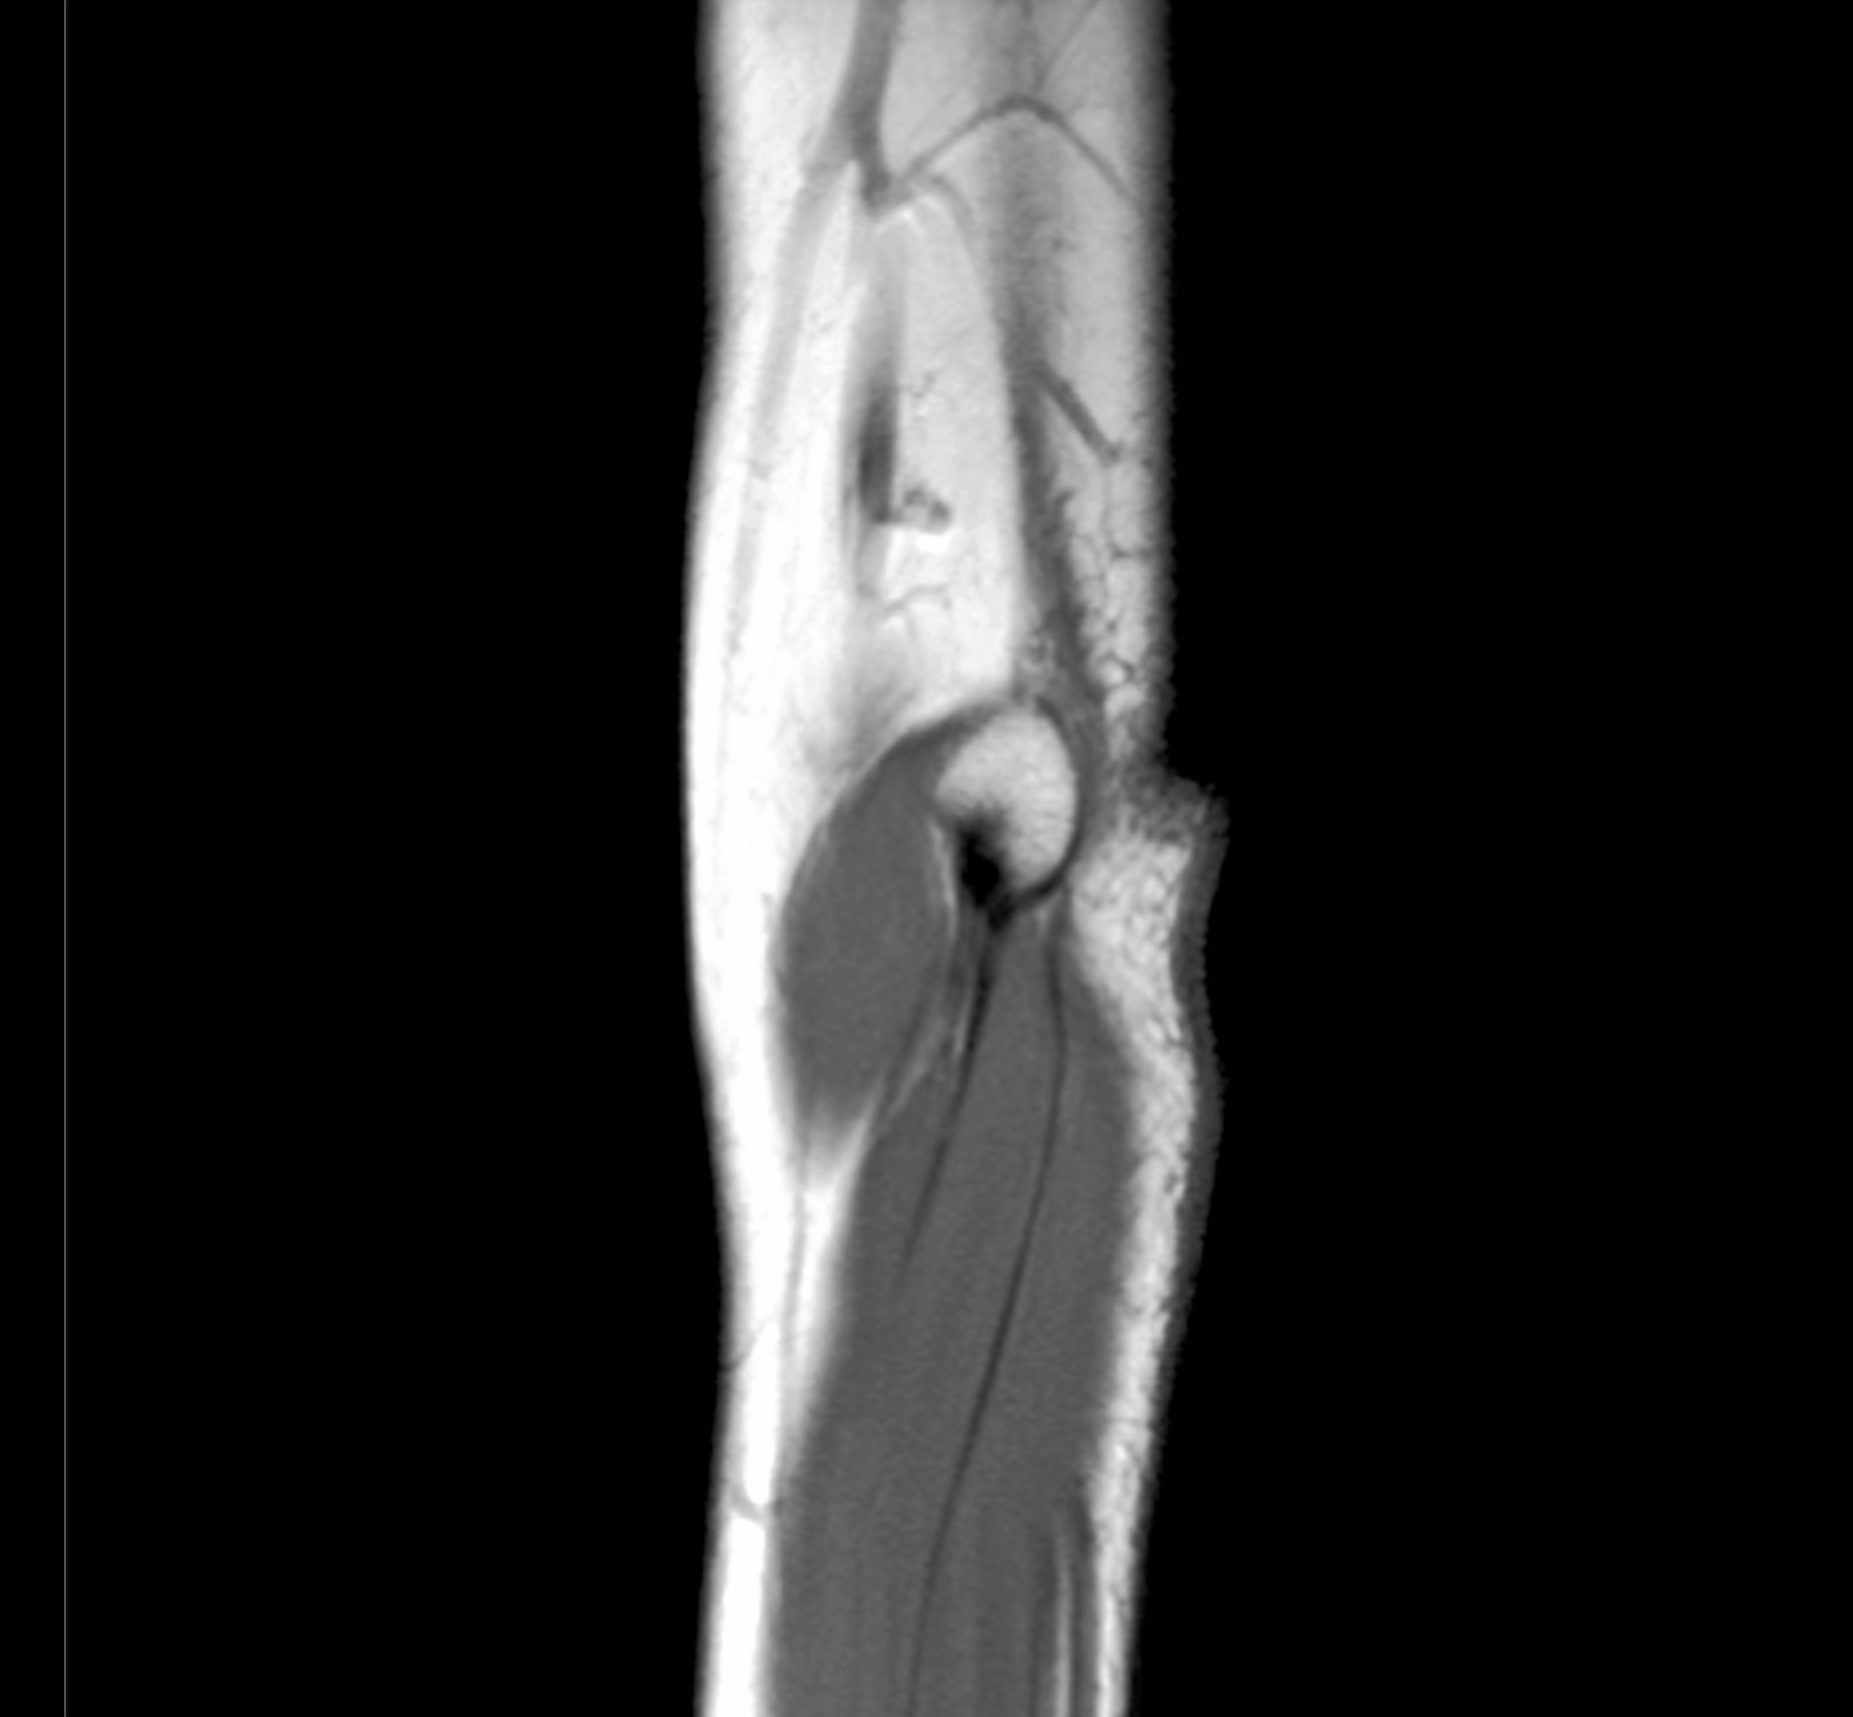

Lecture 25: Cubital Fossa - N. Morales

1. Discuss the boundaries and contents of the cubital fossa. Include fascial specializations, relationships, vasculature, innervation, lymphatics, and clinical significance.

True/False. 1 Point Each.

1. The median cubital vein passes superficial to the bicipital aponeurosis and the brachial artery passes deep to the bicipital aponeurosis. (True)

2. The superior ulnar collateral artery anastomosis with the anterior ulnar recurrent artery within the cubital fossa. (False)

3. The middle collateral artery anastomoses with the interosseous recurrent artery within the cubital fossa. (False)

4. The superior ulnar collateral artery anastomoses with the posterior ulnar recurrent artery within the ulnar canal. (False)

5. The inferior ulnar collateral artery anastomoses with the anterior ulnar recurrent artery within the cubital fossa. (True)

6. The radial collateral artery anastomoses with the radial recurrent artery within the cubital fossa.

7. The ulnar artery passes passes deep to both heads of pronator teres. (True)

8. The median nerve passes deep to the humeral head and superficial to the ulnar head of pronator teres. (True)

9. The radial artery passes superficial to both heads of pronator teres.

10. Entrapment of the median nerve within the pronator teres muscle causes numbness of the distal and proximal regions of the palm. True.

arrowbup Top arrowbdown Bottom